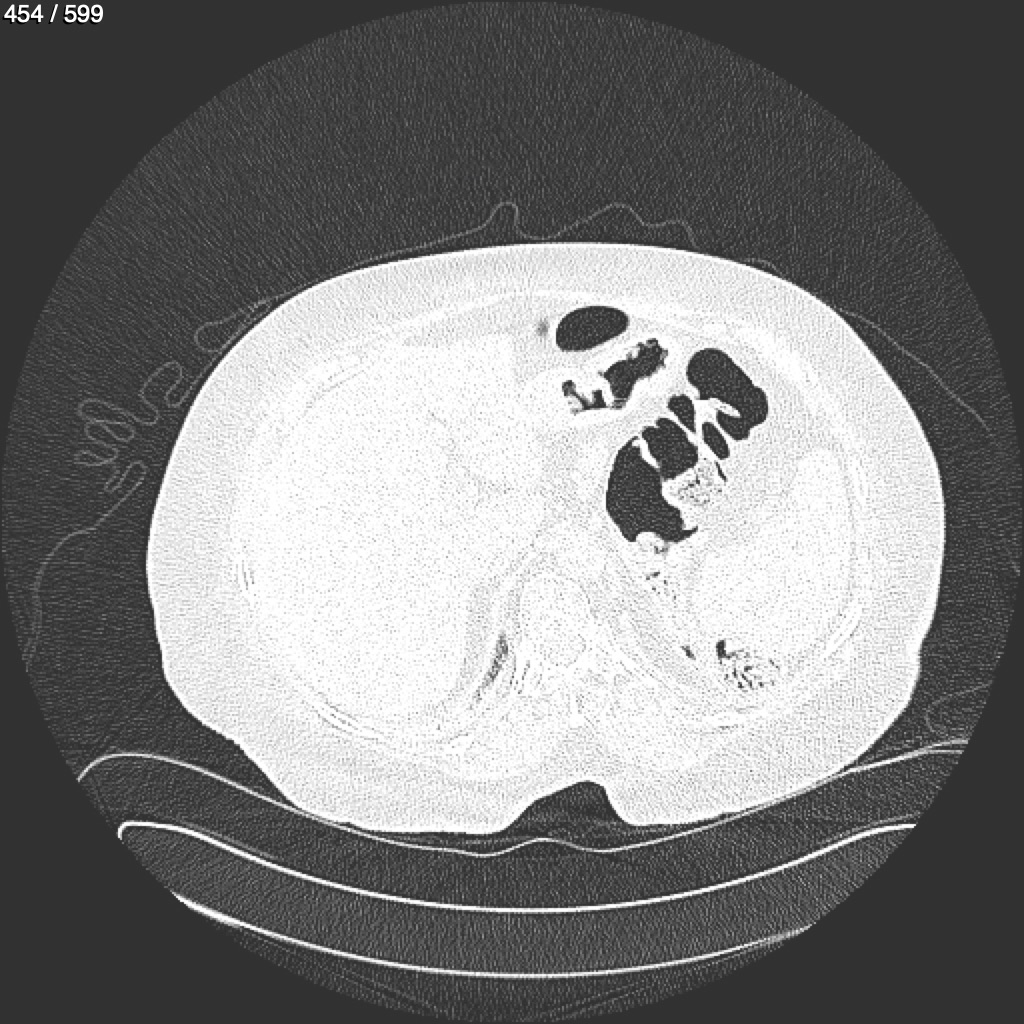

Home G​l​o​r​i​a​ ​G​l​a​d​y​s​ ​B​e​a​s​l​e​y​ ​-​ ​T​ó​r​a​x​ ​T​o​r​a​x​_​S​i​m​p​l​e​ ​(​A​d​u​l​t​o​)